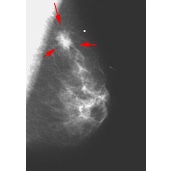

On the mammogram, there are two principal signs of cancer: calcifications and/or the presence of a mass. Calcifications (deposits iof calcium compounds in the breast) show up as white spots on a mammogram and occur in two forms, microcalcifications and macrocalcifications. Macrocalcifications tend to be large and coarse looking and are associated with aging. They are common in women over 50, and are present in a small percentage of younger women. Macrocalcifications are not typically associated with cancer. Microcalcifications are smaller and are considered a sign of possible malignancy, even without a visible mass. The radiologist must interpret the characteristics of the mass to determine the possibility of cancer, and will order diagnostic tests and possibly a biopsy.2

The image on the left shows the mammogram of a normal breast, while the image on the right shows a mammogram with an abnormality detected (denoted by the red arrows). Click on the images to visit their source, the Breast Center of St. Louis University.

Requests for additional testing does not necessarily mean there is anything to fear. The clincians may call a patient back just because something looks a little suspicious and they would like to make a more thorough examination. In the event that a biopsy is indicated the likelihood of cancer is still small. Only 8-10% of those called back will need a biopsy, and approximately 20% of those will be diaganosed as having some form of cancer.2